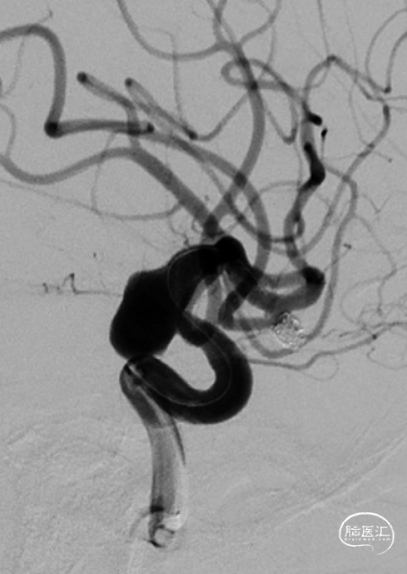

左侧颈内动脉造影:

左侧颈内动脉末端夹层动脉瘤、左侧大脑中动脉分叉部动脉瘤、右侧颈内动脉脉络膜前动脉处动脉瘤。

a.左侧颈内动脉末端夹层动脉瘤形状不规则且囊体较大,大脑中分叉部动脉瘤有一分支发出,这两处动脉瘤相对危险性高,此次优先处理;右侧脉前动脉瘤二期治疗。

b.左侧颈内动脉末端夹层动脉瘤呈不规则长条形改变,脉络膜前动脉在瘤体远端发出,若选用传统的弹簧圈栓塞治疗,则有可能出现分支闭塞,引起并发症,因此考虑使用血流导向装置密网支架覆盖载瘤动脉,避免出现分支血管闭塞。